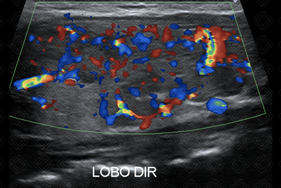

Texto alternativo para a imagem Figura 1. Créditos: Dra. Elazir Mota - Rio de Janeiro/RJ

Descrição das figuras 1 e 2: Ultrassonografia de tireoide evidenciando glândula aumentada, heterogênea, contendo algumas áreas hipoecoicas mal definidas. Ao color Doppler, observa-se aumento difuso da vascularização do parênquima glandular.

• Ultrassonografia de tireoide: Os principais achados são aumento glandular difuso, com parênquima tireoidiano apresentando textura heterogênea, contendo múltiplos pequenos nódulos hipoecoicos, refletindo a infiltração por tecido linfoide e degeneração folicular. Na maioria dos casos, há aumento da vascularização no estudo com Doppler colorido. Em fases mais tardias da doença, a glândula tireoidiana pode apresentar dimensões reduzidas e hiperecoica, com vascularização reduzida ao Doppler colorido, traduzindo evolução para atrofia e fibrose (figura 2).